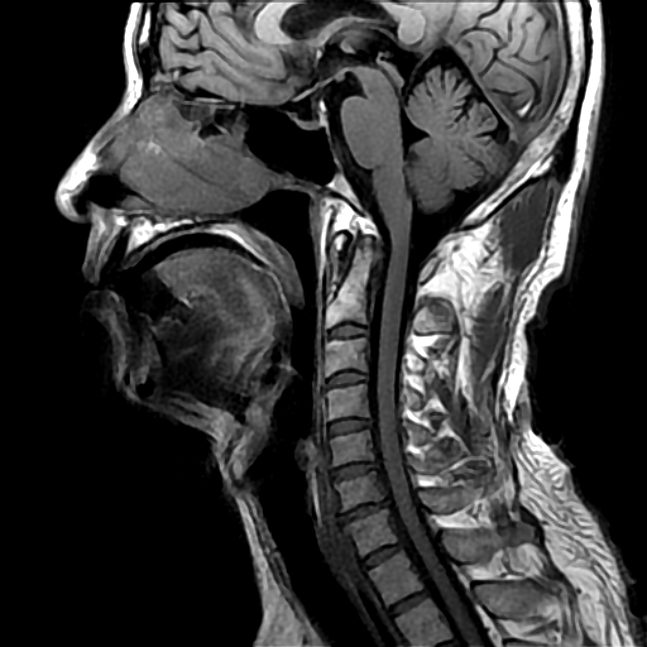

В недавнем исследовании, проведенном в Университете Акдениз в Анталии, Турция, 3D-сканер Artec Eva сыграл важную роль в разработке высокоточного метода отслеживания поведения мягких тканей лица человека. в зависимости от положения тела.

В течение многих лет медицинские эксперты полагались на традиционные методы цефалометрии для изучения пропорций головы и лица. Среди основных решений для сканирования — магнитно-резонансная томография (МРТ), компьютерная томография (КТ) и компьютерная томография с коническим лучом (КЛКТ).Но, как показывает исследование турецких экспертов из Университета Акдениз, результаты традиционных подходов могут содержать неточности.

Проведенное в сочетании с другими методами МРТ и КЛКТ 3D-сканер со структурированным светом Artec Eva, приобретенный университетом у турецкого партнера Artec Teknodizayn, оказался новаторским в минимизации расхождений в измерениях.Его портативный и гибкий дизайн позволил ему обойти ограничения, с которыми сталкиваются традиционные методы. В отличие от Евы, современные медицинские технологии требуют, чтобы пациент оставался стоять, сидеть, или лежать, чтобы отображать биометрические данные. Такое навязывание пациенту и ограничение для практикующего практически устраняются, если вместо этого использовать Eva. Возможность сканировать практически под любым углом увеличивает объем данных, которые могут быть собраны, что, если рассматривать их в целом практикующими врачами, приводит к результатам с превосходной точностью и надежностью.

Во-первых, экспериментаторы стремились исследовать сложность поведения мягких тканей лица человека.В частности, они сосредоточились на степени смещения ткани относительно трех положений тела во время сканирования: стоя, сидя и лежа на спине. Какие изменения можно обнаружить в положении мягких тканей лица при изменении положения тела? И какое отношение эти изменения имеют к медицинским исследованиям и процедурам?

Исследование, проведенное турецкими экспертами, определяет гравитацию как способствующий фактор.Хотя он оказывает на тело силу, его значение по большинству намерений и целей незначительно. Но когда дело касается мягких тканей лица человека, сила тяжести может иметь огромное влияние. Таким образом, исследование возникло из предположения, что данные, полученные с помощью современных методов сканирования, должны быть проанализированы в свете изменчивости изменений, которые гравитационные силы могут создавать из-за изменений положения сканируемого тела.